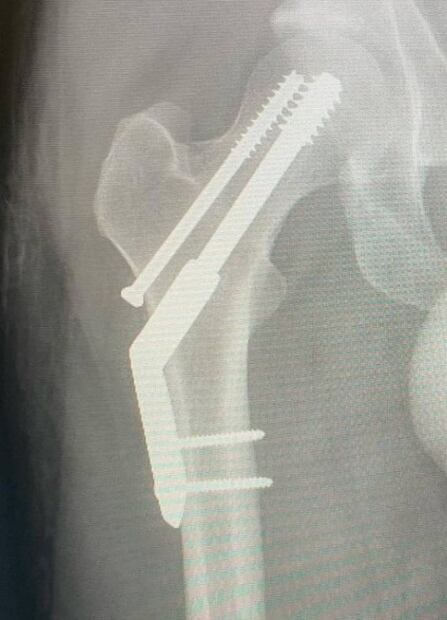

Parker sufrió de una fractura de cadera después de intentar correr un maratón, así lo relató en sus redes, donde está recibiendo el apapacho y los buenos deseos de sus fans:

"Me fracturé la cadera. Intenté correr una media maratón con lo que resultó ser una fractura por estrés. Vaya. Llegué a 1 km de la meta. Así es la vida, supongo", se lee en su mensaje que acompañó con una serie de fotografías.